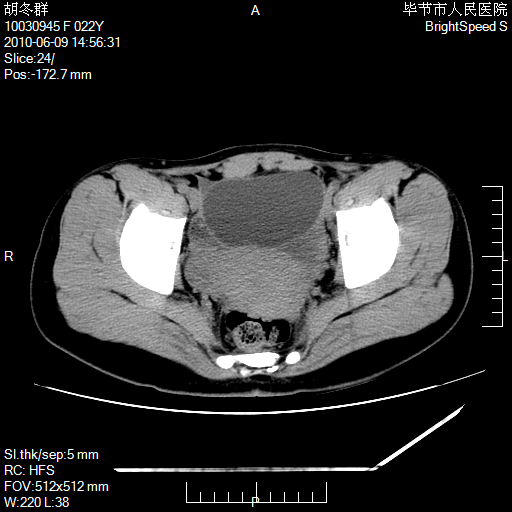

患者23岁,发现腹部包块3月。

左侧卵巢囊腺瘤或囊腺癌

盆腔内囊性占位性病变;考虑左侧卵巢囊腺瘤。

有分隔、壁薄,支持考虑左侧卵巢囊腺瘤。

左侧卵巢浆液性囊腺瘤。

支持考虑左侧卵巢囊腺瘤;宫腔积液。

有分隔、壁薄,支持考虑左侧卵巢囊腺瘤。排尿后,膀胱缩小,由于重力作用,肿块下移就到了膀胱位置,很好理解。